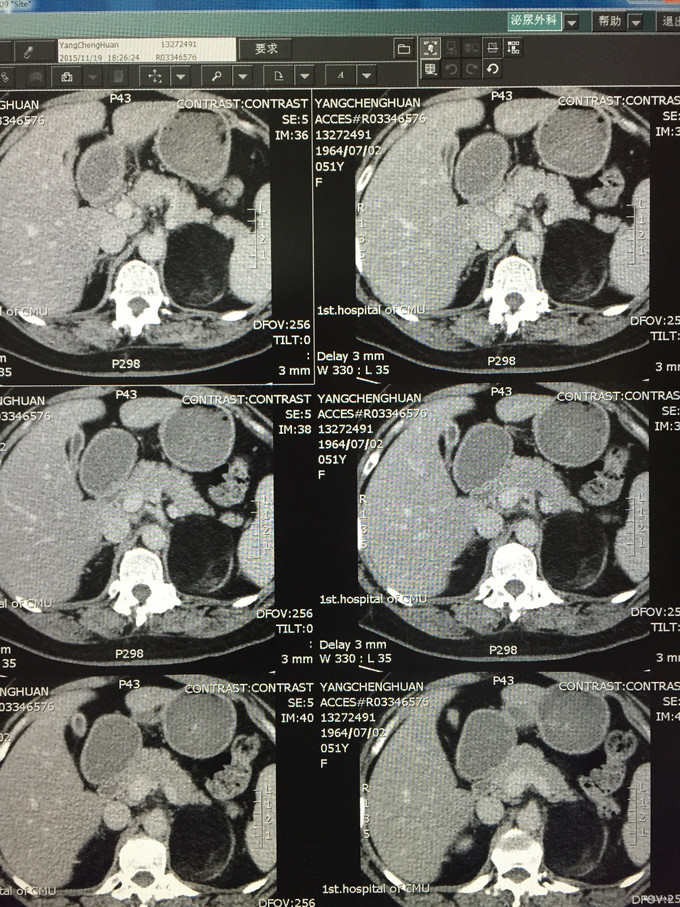

查体,肥胖体型,身高158cm,体重87kg,无满月脸水牛背,皮肤紫纹,毳毛增多等皮质醇症外貌特征 辅查:血钾正常,肾上腺激素系列均未见明显异常。 超声:左肾上腺高回声实质性包块,大小约8.1*5.5cm,局部未测及有效血流信号 肾上腺增强CT:左肾上腺区可见类圆形异常密度影,大小约7.6*5.6cm,边界清晰,已脂肪密度为主,CT值-88Hu,其内可见软组织条片影,增强后可见强化,提示左肾上腺占位性病变,髓性脂肪瘤可能性大,

诊断:左肾上腺髓性脂肪瘤 治疗:全麻后腹腔镜下左肾上腺及肿瘤切除术 病理诊断:髓性脂肪瘤